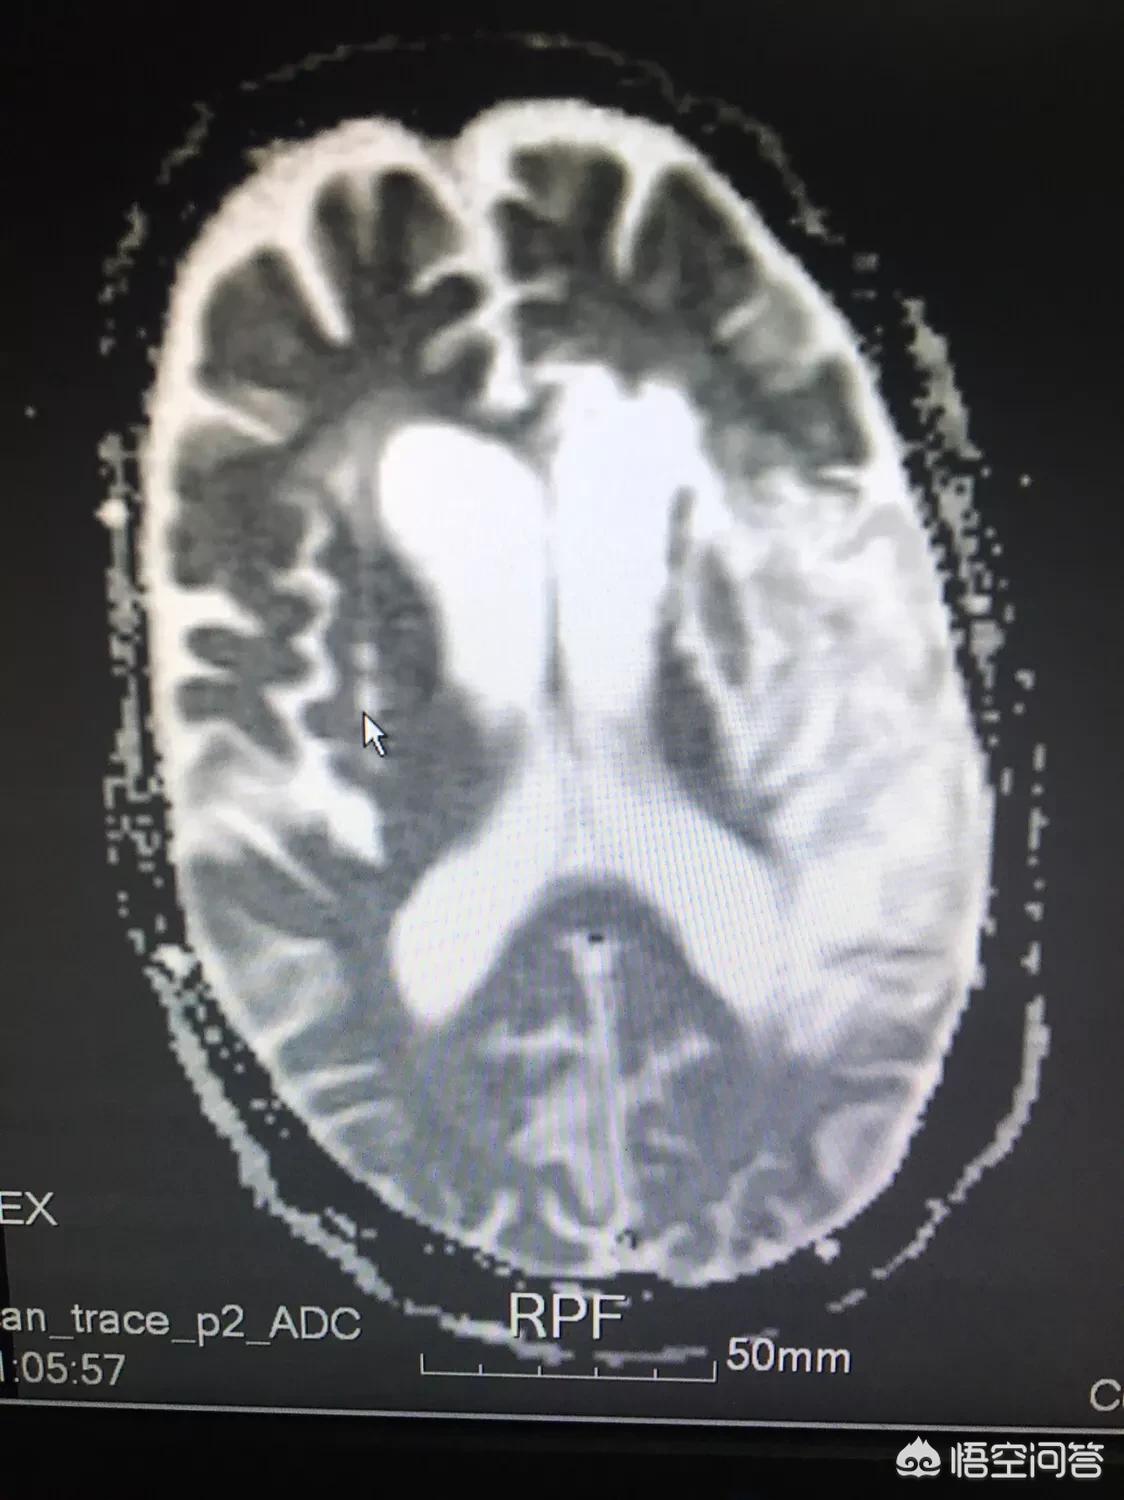

脑梗塞的病人都会查一下颈部血管的情况,如颈部CTA/颈部血管彩超,如果发现有血管狭窄,而刚好又是这根狭窄的血管导致的脑缺血,就说这是责任血管,一方面是寻找原因,同时也有利于评估病人的预后。比如,我有一个病人大面积脑梗塞,一侧颈内动脉狭窄,病人症状很重,病情稳定后来康复,吞咽障碍/言语不利/半身不遂,很多功能都受到影响,而且我们根据病变部位,大概估计恢复不好。